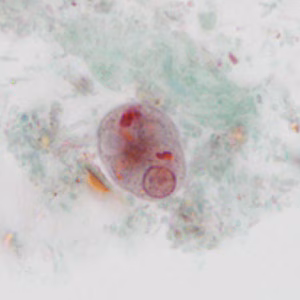

Stool specimens were collected from an asymptomatic 10-year-old boy from Panama as part of a refugee screening program. The stool was collected in 10% formalin and zinc PVA (Zn-PVA) and sent to the county health department for routine ova-and-parasite (O&P) examination. Figures A – I show what was observed at 1000x magnification with oil on a trichrome-stained slide made from stool preserved in Zn-PVA. Objects in Figures A and G measured approximately 10 micrometers; all other objects of interest ranged from 17-25 micrometers. Figures C – E show different focal planes of the same object of interest to highlight internal structures. What is your diagnosis? Based on what criteria?

Figure B